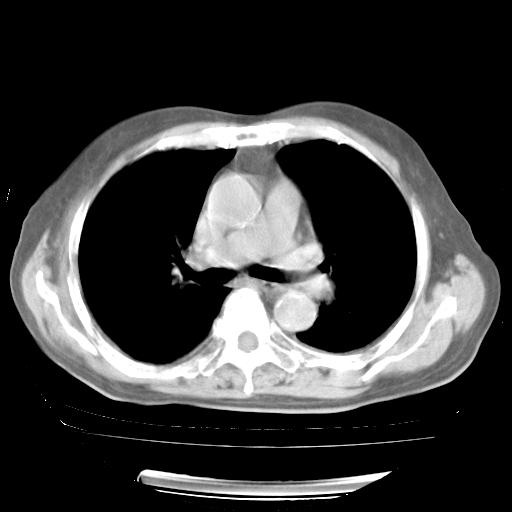

4月28日肺部CT——再次出现类似去年5月9日——透光度降低,“间质性”改变。

4月28日肺部CT——再次出现类似去年5月9日——磨玻璃样、间有“粟粒样”改变。